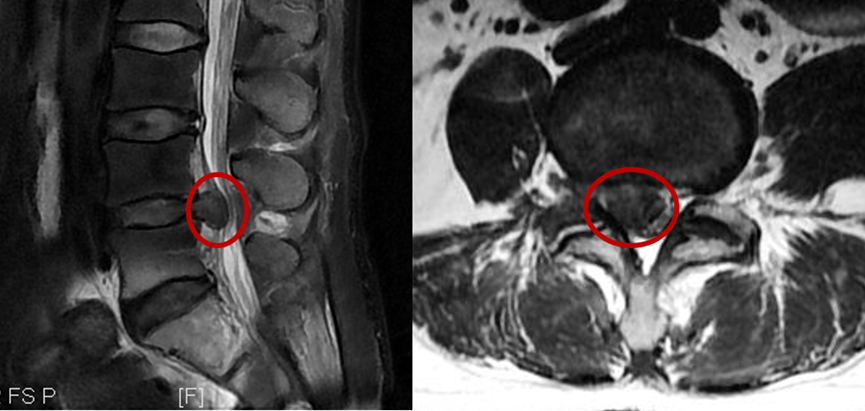

腰椎MR显示腰椎间盘突出,压迫右侧神经根

汪洋主任讲到,腰椎间盘的损伤就像"温水煮青蛙",早期干预可避免80%的手术风险。初期建议保守治疗,通过理疗,再搭配复健,并且要多休息,通常会有改善。部分患者因严重压迫到神经,或是造成神经问题,则需要进行微创或手术治疗。别让一时的疏忽,成为终身的遗憾!腰椎间盘突出具体采用什么疗法,请依据医生的诊断和指导,结合个人的实际病情严重程度来决定。